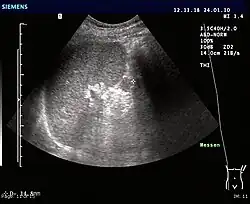

Ultrasonography of an accessory spleen.